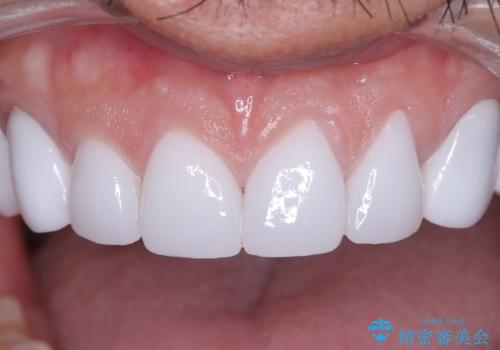

前歯のクラウンをやり変え、歯肉のラインも美しく

- 治療計画

治療では、まず古いクラウンを慎重に取り外し、歯肉の状態を整えました。その後、精密な型取りから患者様一人ひとりに合わせたオーダーメイドのオールセラミッククラウンを作製。金属を一切使用しないため、歯肉の変色を防ぎ、天然歯のような透明感と美しさを再現します。新しいクラウンは、歯肉のラインに合わせてぴったりと適合するよう調整し、見た目の違和感を解消。長年の悩みが解決し、自然で美しい口元と笑顔を取り戻していただけました。